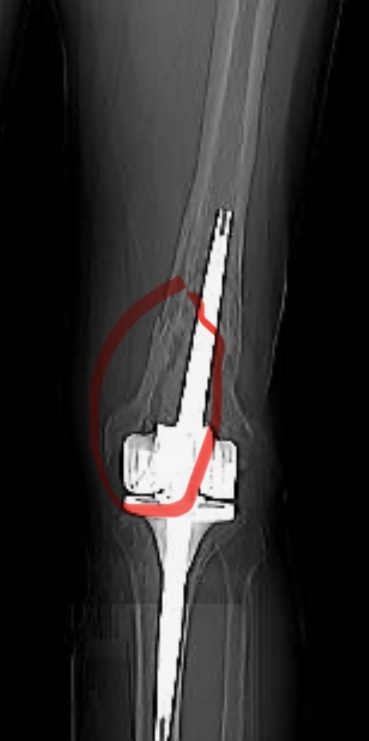

1989 hatte ich einen schweren Verkehrsunfall zwischen Murnau am Staffelsee und Weilheim in Oberbayern, hier bei erlitt ich ein Polytrauma (offenen Oberschenkel-Bruch rechts,Wadenbein offen gebrochen, Kreuzbandriss, rechts, offenen Oberarmbruch links, Kreuzbandriss links sowie Kondylenzertrümmerung linker Oberschenkel) 2010 wurden die Schmerzen im linken Knie so schlimm, das eine Knie-Prothese (TEP) eingesetzt werden musste. Im Jahr 2020 bestand der Verdacht auf Innenbandriss im linken Knie, das Band war nicht gerissen, aber dafür wurde festgestellt, das sich die Knieprothese locker. Also wurde ein Prothesenwechsel vorgenommen. 2022 hat sich das künstliche Kniegelenk entzündet und musste ersetzt werde, da eine Behandlung der Entzündung mit Antibiotika von außen her nicht möglich ist. Ende 2023 hat sich die Prothese erneut gelockert, ein Wechsel war für Oktober 2024 geplant. Im Juni 2024 wurde ei CT für die Voruntersuchung gemacht, hier hat sich dann herausgestellt, dass der Oberschenkel Kniegelenks nah gebrochen ist. Der Bruch scheint ca. 3 bis 5 Monate alt zu sein, diesen habe ich nicht gemerkt, da ich auf Schmerzmittel eingestellt gewesen bin.